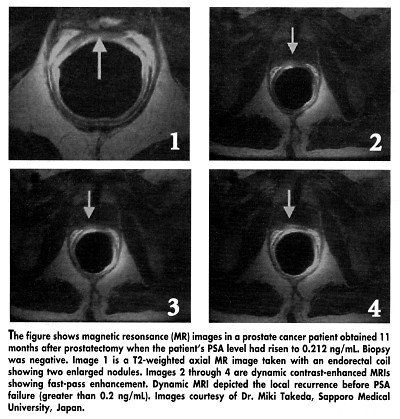

To test the ability of MRI to predict local recurrence, Dr. Takeda and her colleagues evaluated 21 patients with rising PSA levels who had undergone a radical prostatectomy. They examined the prostatic fossa with T2-weighted images. After a bolus injection of a gadolinium contrast agent, multisectional dynamic MR images were obtained every 10 to 15 second for 90 seconds (see Figure).

Although all patients had a negative ultrasound-guided biopsy, MRI suggested local recurrence in 17 of the 21 patients. "In most cases, a second or third biopsy would have been needed to confirm recurrence, and this takes timetime in which the patient’s PSA level may continue to rise," Dr. Takeda said.